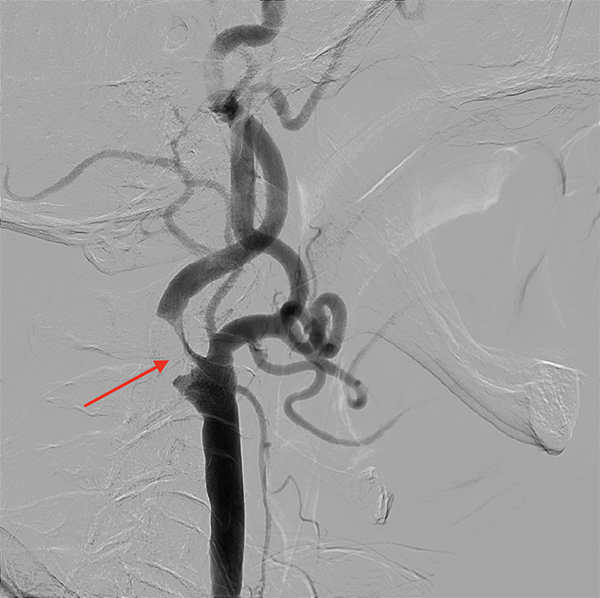

実際の症例